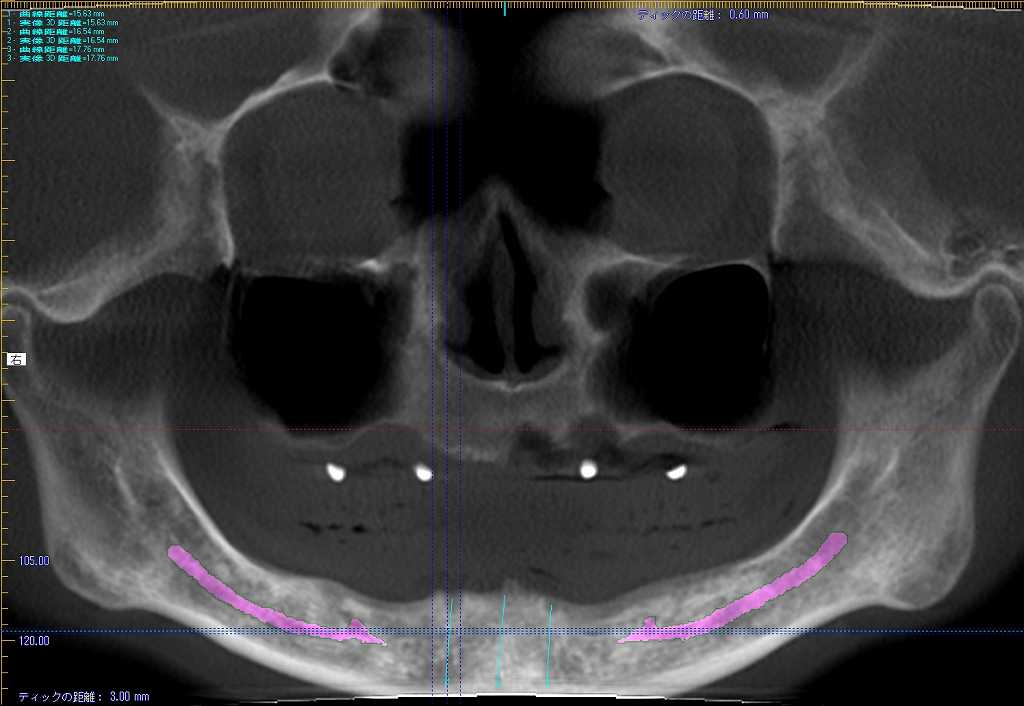

インプラント埋入時になります

3本とも4mmの13mmというインプラントを埋入

術前術後のパノラマになります

インプラントはオペ時に5本入れていることになります